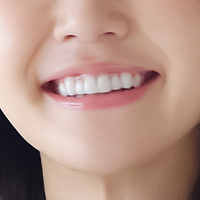

この患者さんは、前歯の仮歯を治したいという主訴にいらっしゃいました。

この患者さんの問題は噛み合わせが崩れてしまっていることにより、

前歯の長さやバランスが悪くなっていることでした。

患者さんに説明し、総合治療をご希望されたため、

技工士さんと協力し、診断、治療用の仮歯を制作、治療しました。

初診時

仮歯 (治療回数1回 所要時間 約2時間)